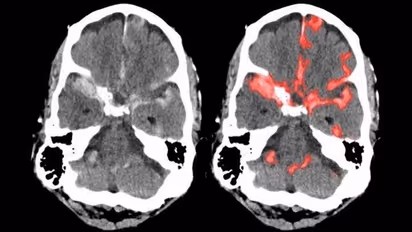

ಅದರಂತೆ ಮಾರಣಾಂತಿಕ ಬ್ರೈನ್ ಹ್ಯಾಮ್ರೇಜ್'ನ್ನು ಆರಂಭಿಕ ಹಂತದಲ್ಲೇ ಗುರುತಿಸಬಲ್ಲ ಹೊಸ ಎಐ ತಂತ್ರಜ್ಞಾನವನ್ನು ಭಾರತೀಯ ಮೂಲದ ವೈದ್ಯರು ಸಂಶೋಧಿಸಿದ್ದಾರೆ.

ಯುಸಿ ಬರ್ಕ್ಲಿ ಹಾಗೂ ಯುಸಿ ಸ್ಯಾನ್ಫ್ರಾನ್ಸಿಸ್ಕೋ ವೈದ್ಯರಾದ ಜಿತೇಂದ್ರ ಮಲಿಕ್ ಹಾಗೂ ಪ್ರತೀಕ್ ಮುಖರ್ಜಿ, ಬ್ರೈನ್ ಹ್ಯಾಮ್ರೇಜ್ ಲಕ್ಷಣಗಳನ್ನು ಗುರುತಿಸಬಲ್ಲ ಆರ್ಟಿಫಿಶಿಯಲ್ ಇಂಟೆಲಿಜೆನ್ಸ್ ಯಂತ್ರವನ್ನು ಸಂಶೋಧಿಸಿದ್ದಾರೆ.

ರೋಗಿಯ ಮೆದುಳಿನಲ್ಲಿ ಜರಗುವ ಅಸಹಜ ಪ್ರಕ್ರಿಯೆಗಳನ್ನು ಪಿಕ್ಸೆಲ್ಗಳಲ್ಲಿ ಸೆರೆ ಹಿಡಿದು ನಂತರ ಅದನ್ನು ಕೇವಲ ಸೆಕೆಂಡ್ನಲ್ಲಿ ಸ್ಕ್ಯಾನ್ ಮಾಡಬಲ್ಲ ಸಾಮರ್ಥ್ಯ ಈ ಎಐ ಯಂತ್ರಕ್ಕಿದೆ ಎಂದು ಈ ವೈದ್ಯರು ಮಾಹಿರತಿ ನೀಡಿದ್ದಾರೆ.